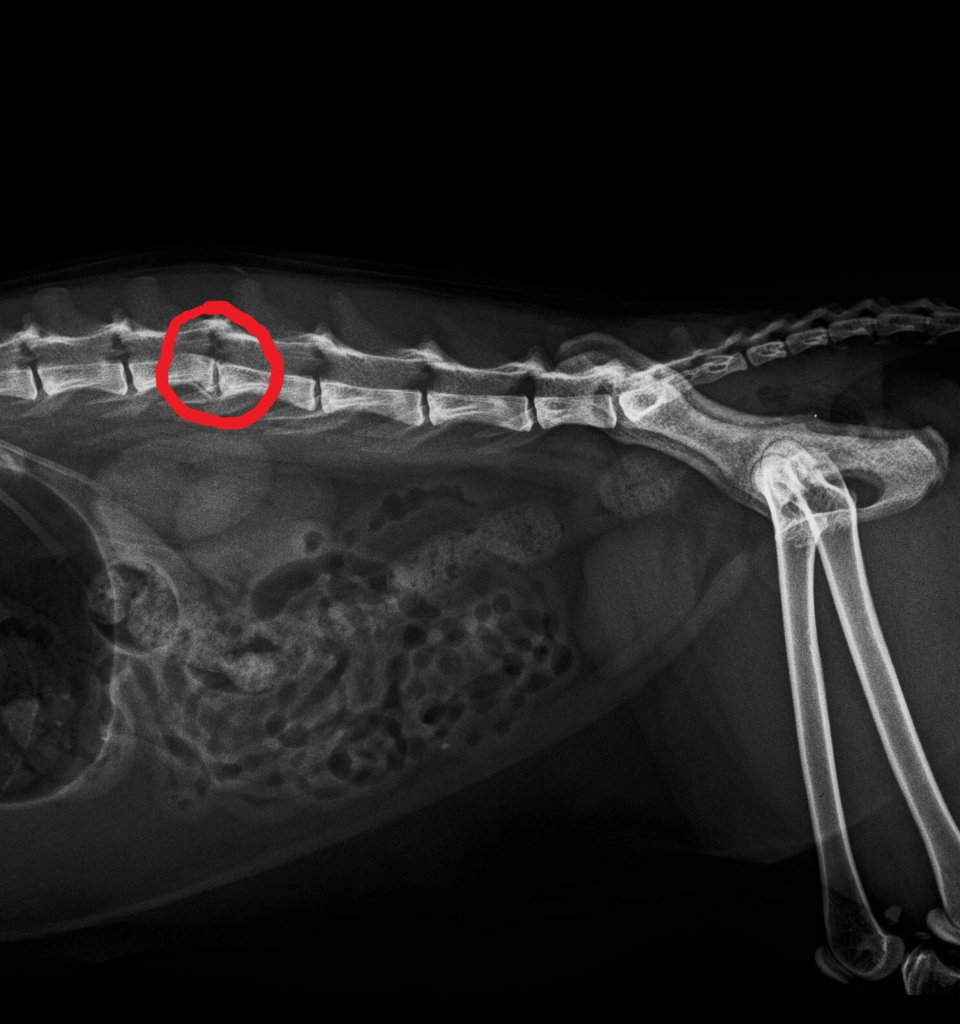

Presso la Clinica Veterinaria San Carlo è attivo il servizio di radiologia veterinaria, fondamentale sia per la diagnosi che per la prevenzione di numerose patologie nel cane e nel gatto.

La struttura è dotata di un apparecchio radiologico ad alta frequenza, che consente di eseguire esami radiografici di elevata qualità su animali di qualsiasi taglia, garantendo immagini precise e affidabili.

La radiologia riveste un ruolo centrale anche nell’ambito della medicina preventiva, in particolare per la diagnosi precoce delle malattie scheletriche ereditarie, come la displasia dell’anca e del gomito nei cani.

Nelle razze predisposte e a rapido accrescimento, tra cui Pastore Tedesco, Labrador Retriever, Boxer, Alano, Pitbull, Cavalier King Charles Spaniel e Bulldog, è consigliato effettuare radiografie precoci a partire dai 4 mesi di età, così da individuare eventuali alterazioni articolari prima della comparsa dei sintomi clinici e pianificare tempestivamente il percorso terapeutico più adeguato.